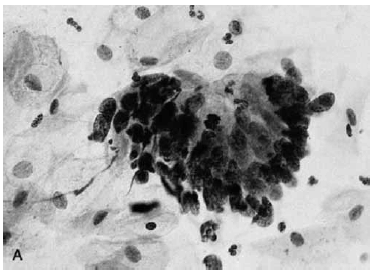

Nas questões de números 46 a 60, assinale a alternativa que melhor corresponde ao diagnóstico do quadro microscópico apresentado.

Adenocarcinoma in situ.

Carcinoma escamoso in situ.

Carcinoma escamoso invasivo.

Atrofia.

Lesão intraepitelial escamosa de baixo grau.